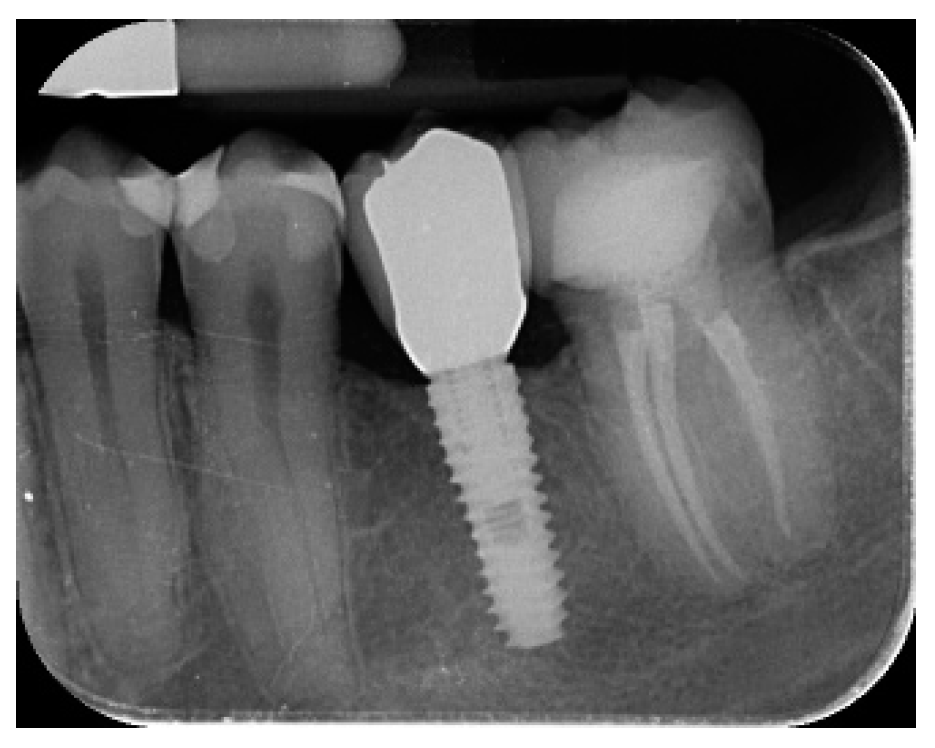

- Marginal bone level changes were assessed by digital periapical radiographs (Digora Optime; Soredex, Tuusula, Finland) using the parallel technique and commercially available film holders. Three time points were evaluated, at implant placement (baseline), immediately after the insertion of the restoration, and one year after loading. The averaged mesial and distal distances from the most coronal margin of the implant and the first bone-to-implant contact was measured to the nearest 0.01 mm and taken as the marginal bone level. The difference in levels between time points was taken as marginal bone loss (MBL).

| Mean marginal bone loss (mm) | 0.13 ± 0.09 (95% CI 0.08–0.19) | 0.28 ± 0.33 (95% CI 0.07–0.50) |